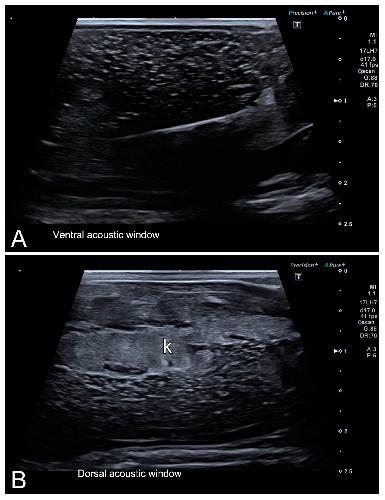

Figure 7. Representative HR-US images of Kaloula pulchra (A) and Xenopus laevis (B) males obtained in the longitudinal plane using a dorsal acoustic window. The testes (delimited by arrows) appeared as structures with oval morphology, mid echogenicity and homogenous echotexture. Testes were located just ventral or ventrolateral of the ipsilateral kidney (k).

|